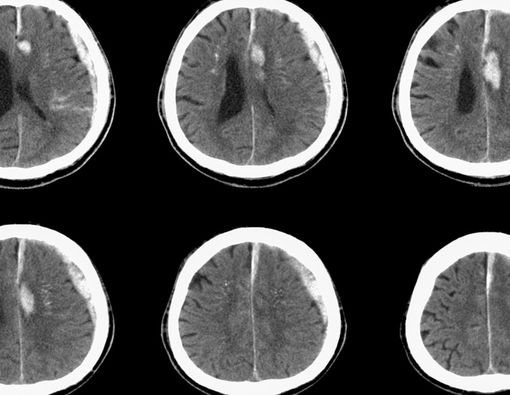

Hematoma subdural (SDH atau subdural hematoma) merupakan perdarahan di antara lapisan otak, yakni lapisan arachnoid dan lapisan dura (meningeal).

"Ada tiga tipe SDH berdasarkan waktunya, yaitu SDH akut, SDH subakut, dan SDH kronis. SDH akut terjadi kurang dari 72 jam, SDH subakut 3-7 hari setelah cedera, dan SDH kronis terjadi dalam beberapa minggu," ungkap dr. Sepriani Timurtini Limbong.

Beberapa kasus hematoma subdural dapat menyebabkan komplikasi serius, termasuk koma atau bahkan kematian. Hal ini dapat terjadi bila tidak diobati atau bahkan terkadang muncul setelah pengobatan.

Komplikasi yang mungkin terjadi adalah herniasi otak. Herniasi otak adalah tekanan di otak yang dapat menjauhkan jaringan dari tempatnya semula. Kondisi ini bisa menyebabkan kematian.

"Penanganannya tergantung derajat keparahan. Biasanya akan dilakukan pemeriksaan dulu, seperti MRI atau CT scan. Kemudian, ditentukan apakah harus dilakukan pembedahan atau ada pilihan lain," ungkap dr. Sepriani.